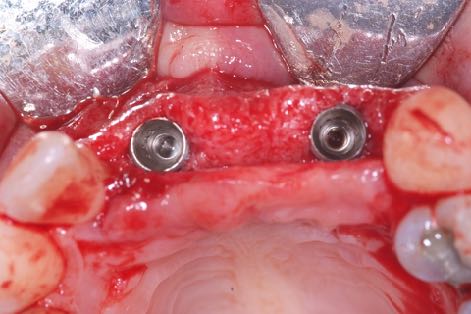

La stabilité secondaire c’est l’ostéo-intégration, et c’est assurément notre objectif ultime. Idéalement, le but est d’obtenir une stabilité secondaire suffisante le plus rapidement possible pour restaurer chez nos patients une fonction normale avec leurs restaurations des couronnes implanto-portées.

Je suis convaincu que le maintien de l’os marginal péri-implantaire est l’un des facteurs clés de prévention des complications biologiques futures. Par conséquent, si l'on arrive à obtenir une stabilité secondaire en minimisant les lésions osseuses au niveau cellulaire, les conditions d’une réussite prévisible durable sont presque entièrement remplies.